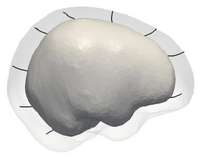

Intracranial evo.png

Smooth Growth Trajectories from Time Series Shape Data

Ongoing: Clinical research is interested in the spatiotemporal analysis of changes of anatomical shapes and structures, which potentially leads to improved understanding of the rate of change, locality and growth trajectory of structures of interest. This project develops a new methodology for the generation of a continuous growth model generated from a sparse set of shapes. More...

Fishbaugh, J., Durrleman, S., Gerig, G. Estimation of Smooth Growth Trajectories with Controlled Acceleration from Time Series Shape Data. Proc. of Medical Image Computing and Computer Assisted Intervention (MICCAI '11). September 2011.